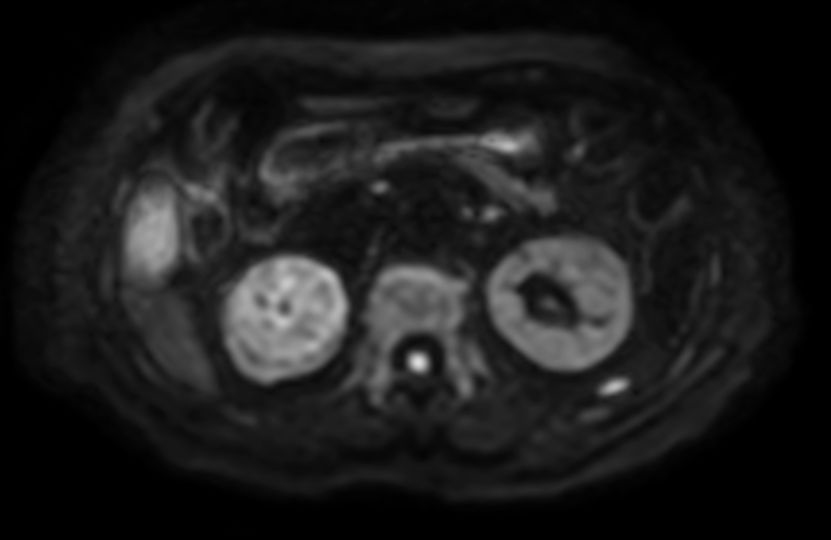

Diffusion b800 (ADC) - Free Breathing

-